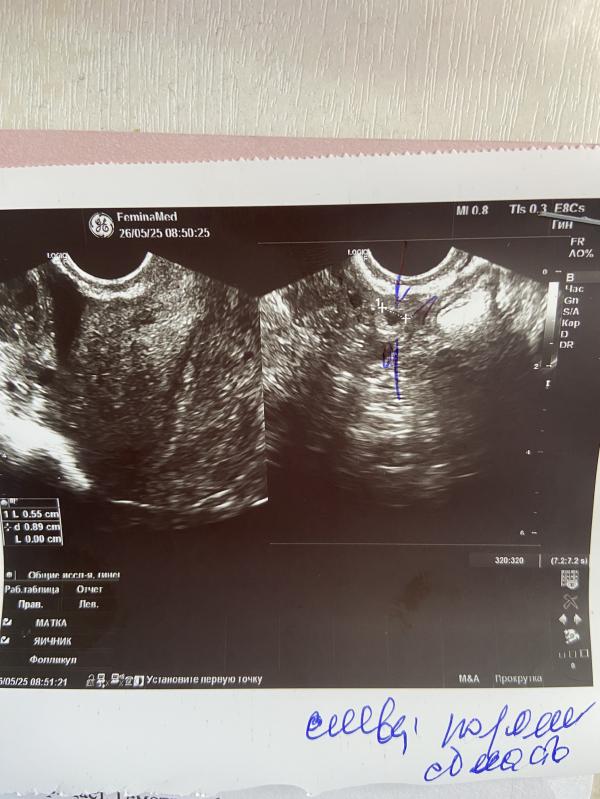

Желтое тело справа , какая то точка слева . Плодного яйца нет , отправили на повторный хгч . Подвешенное состояние , надеялась что что то проясниться , но увы.

@mary_mur_, @faraonka, в четверг было 480 , уехала на отдых , вот пошла утром , должно уже быть около 2000 . Вот сдала опять ( завтра будет видно есть что искать или нет

Ну вообще уже должен быть больше 1000